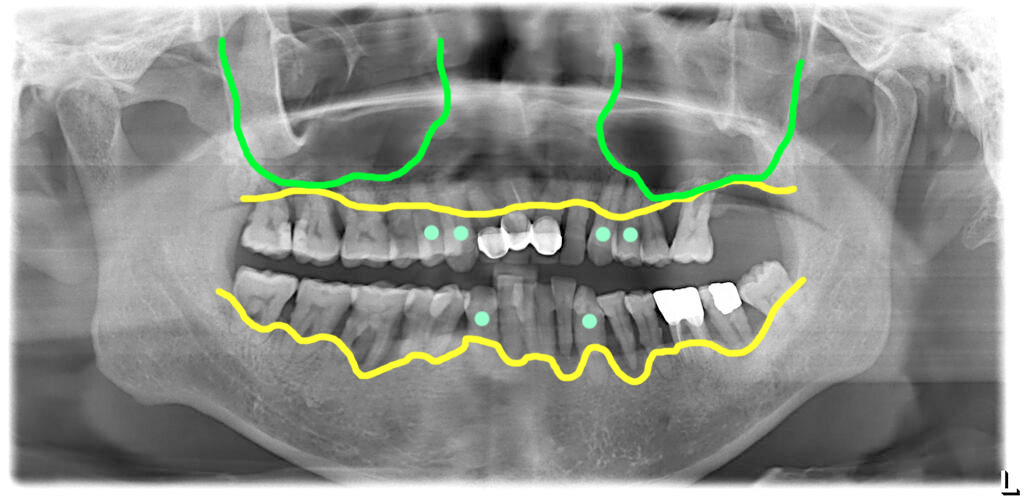

2018년 초진시 6개 치아 살리기로 계획

처음 병원에 오셨을 때의 상태는 전체적으로 치주염이 심했으며, 앞니 보철의 경우 보철 안쪽에서 치아들이 충치가 진행되어 있어 전체적인 치료가 필요하다고 결정했어요.

하지만 당시 일부 치아 #13, #14, #23, #24, #33, #43 (하늘색)는 뽑지 않고 살려서 치료를 하기로 했습니다. 해당 치아들을 살리기로 했지만 치주상태가 좋지 않고 전체적인 조화를 고려해서 신경치료 후 크라운 치료를 하기로 했습니다.

위쪽 어금니 부위는 상악동 영역이 크고 뼈가 부족해서 상악동 거상(윈도우수술)이 필요하다고 설명했어요.